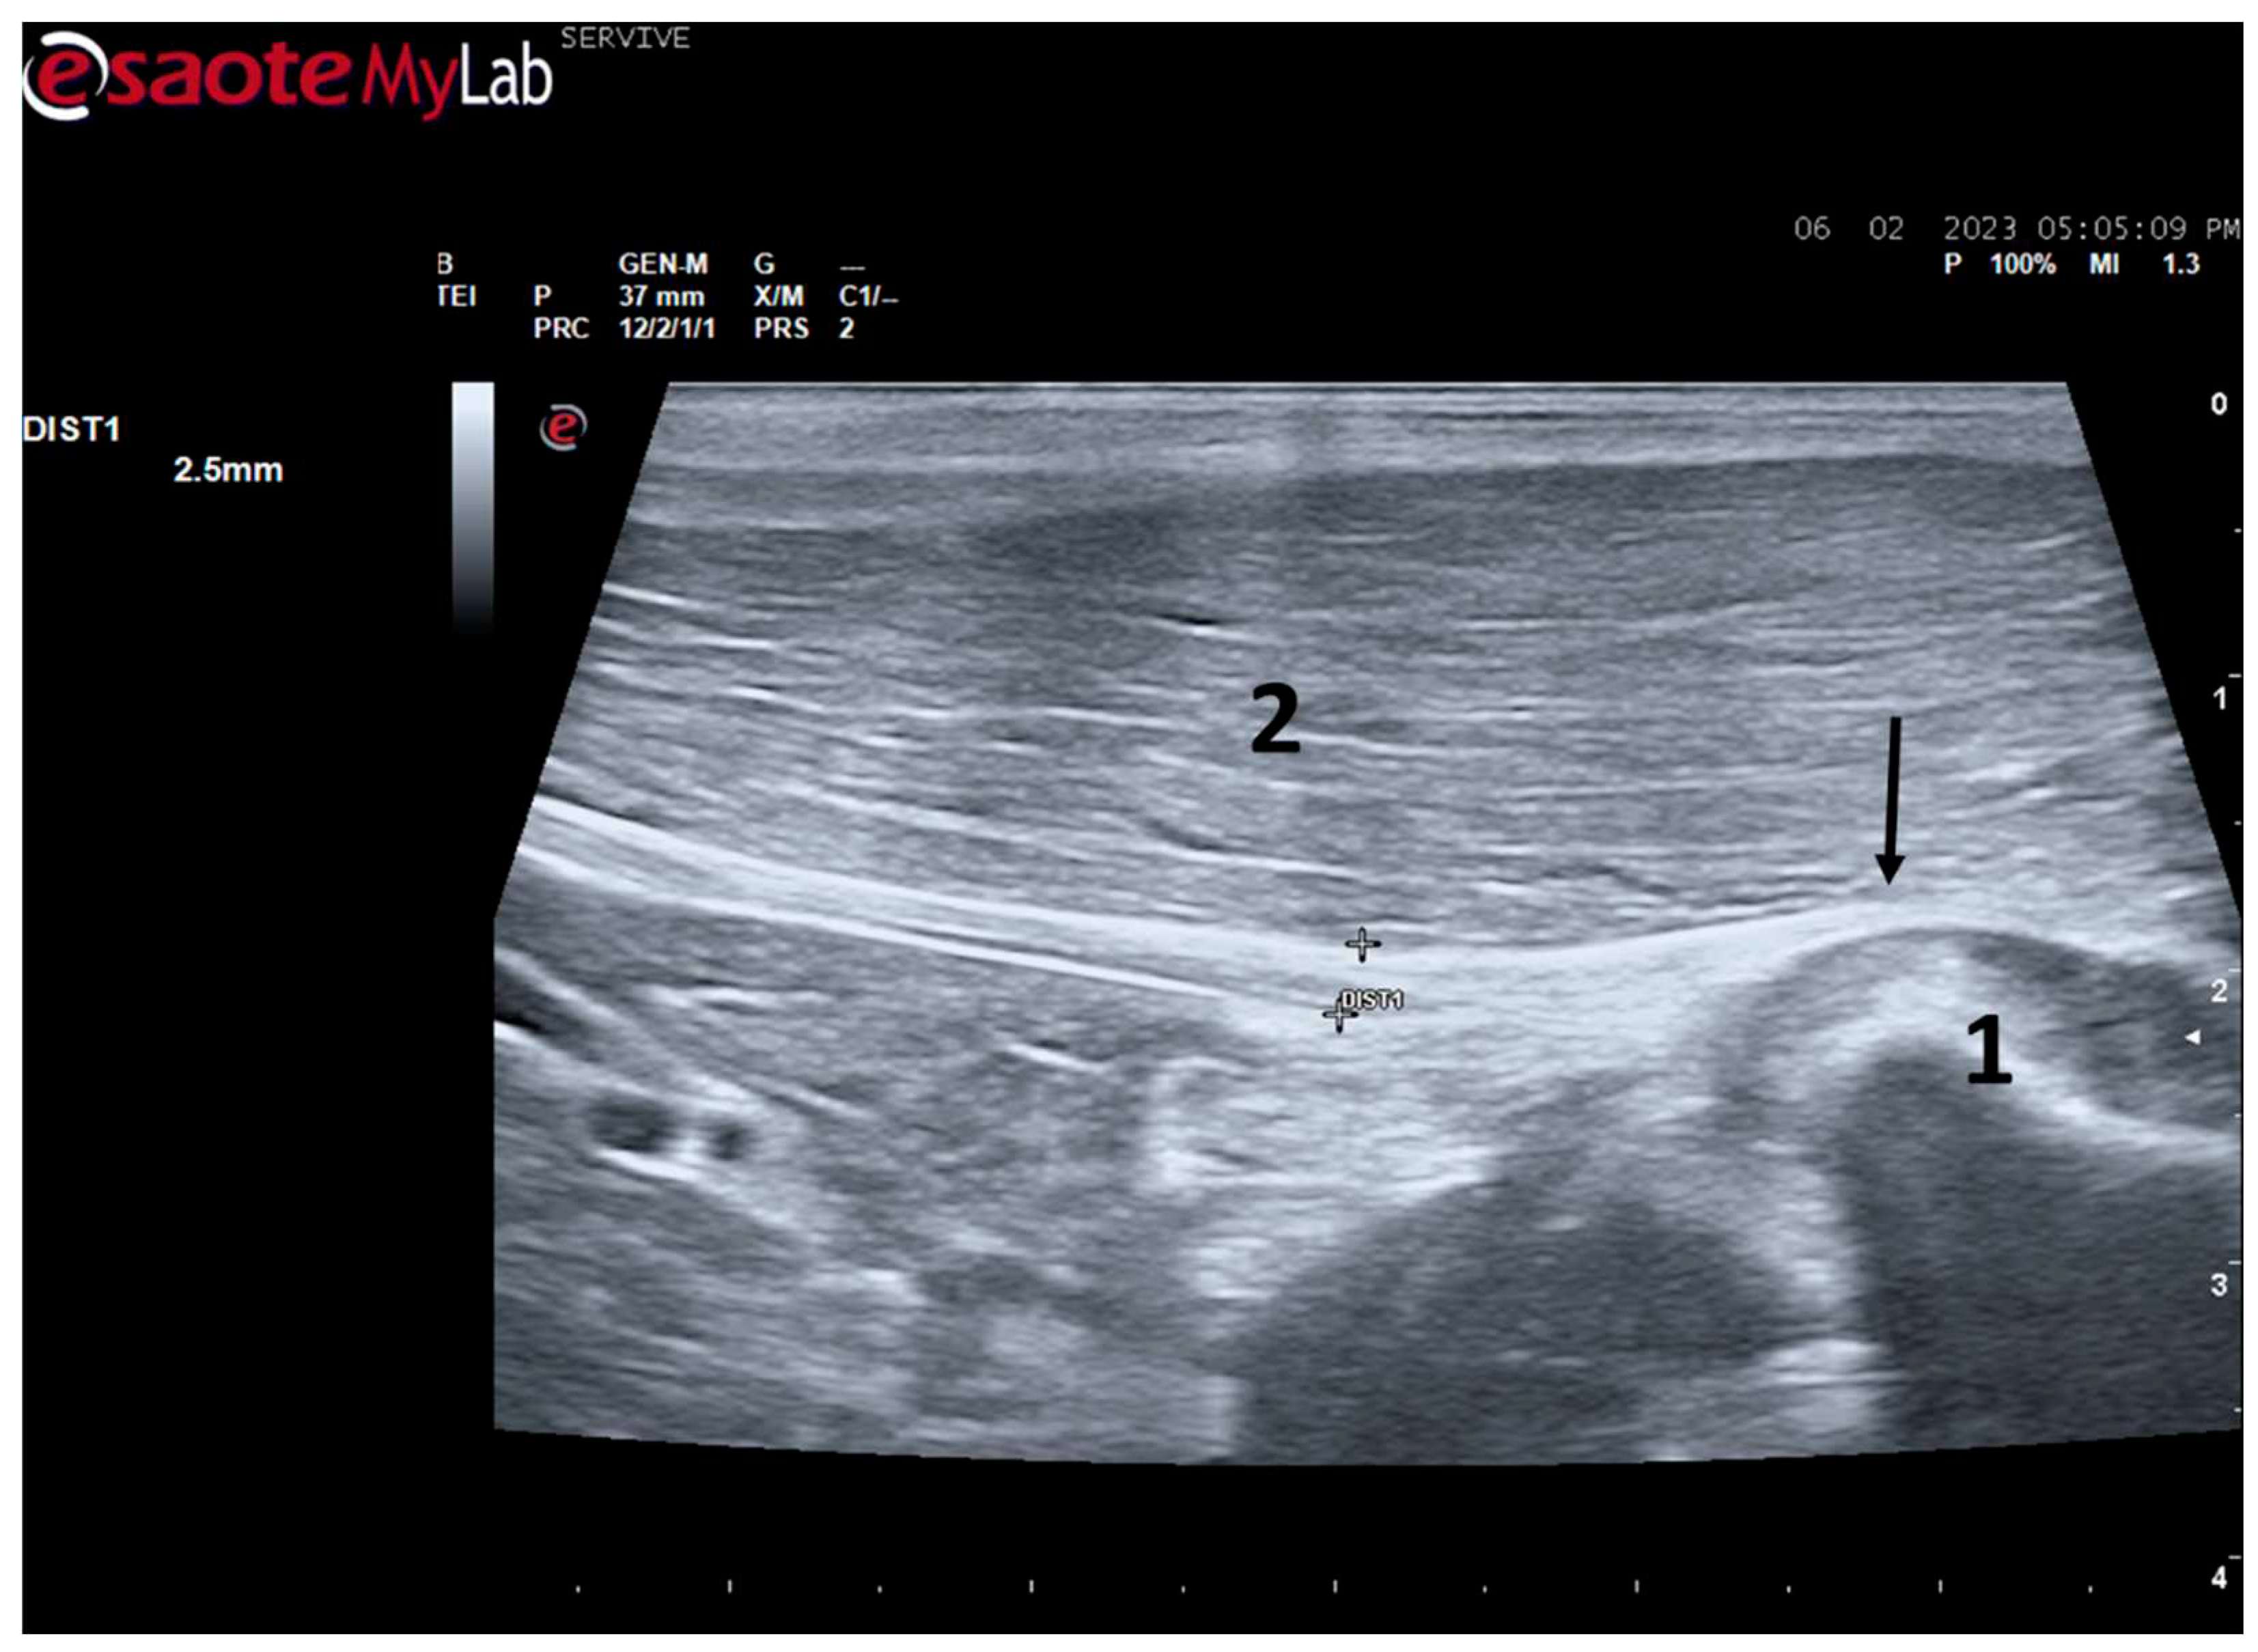

Figure 8.

Ultrasound image of the left sciatic nerve before its branching site, cross section (black arrow). In this plane, the nerve appears as an echogenic tubular structure surrounded by the musculature of the region. 1) biceps femoris muscle; 2) vastus lateralis muscle; 3) adductor muscles. DIST1 represents the measurement of the diameter of the sciatic nerve before its branching site.

Figure 8). Obtaining an image in this plane proved to be more complex and made it difficult to establish anatomical relationships with neighboring structures and with the ramifications of the sciatic nerve. On the other hand, the ultrasound image reveals echographic characteristics identical to those obtained in the regular plane, in addition to the measured diameter being the same as that obtained with the previous technique. Therefore, it was decided not to use the transverse plane for this echographic characterization in any of the considered nerves.